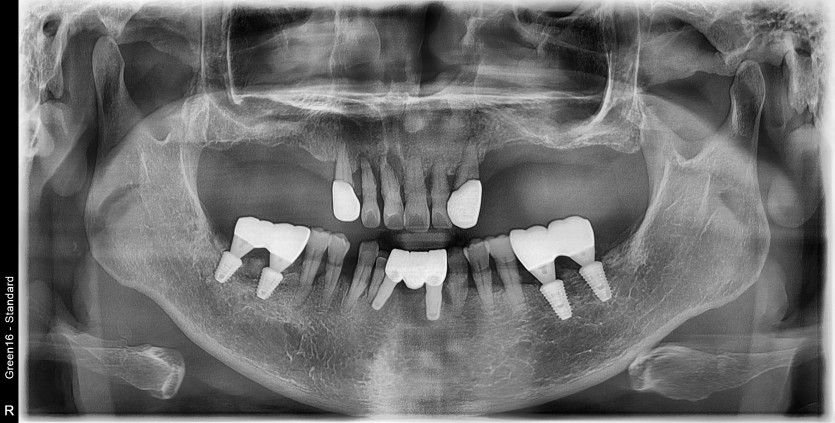

만 63세 전체 임플란트 증례(기존 임플란트 포함)

전체 임플란트 증례입니다.

(기존 임플란트 포함하여 교합 안정화)

16개의 임플란트로 완성하였습니다.